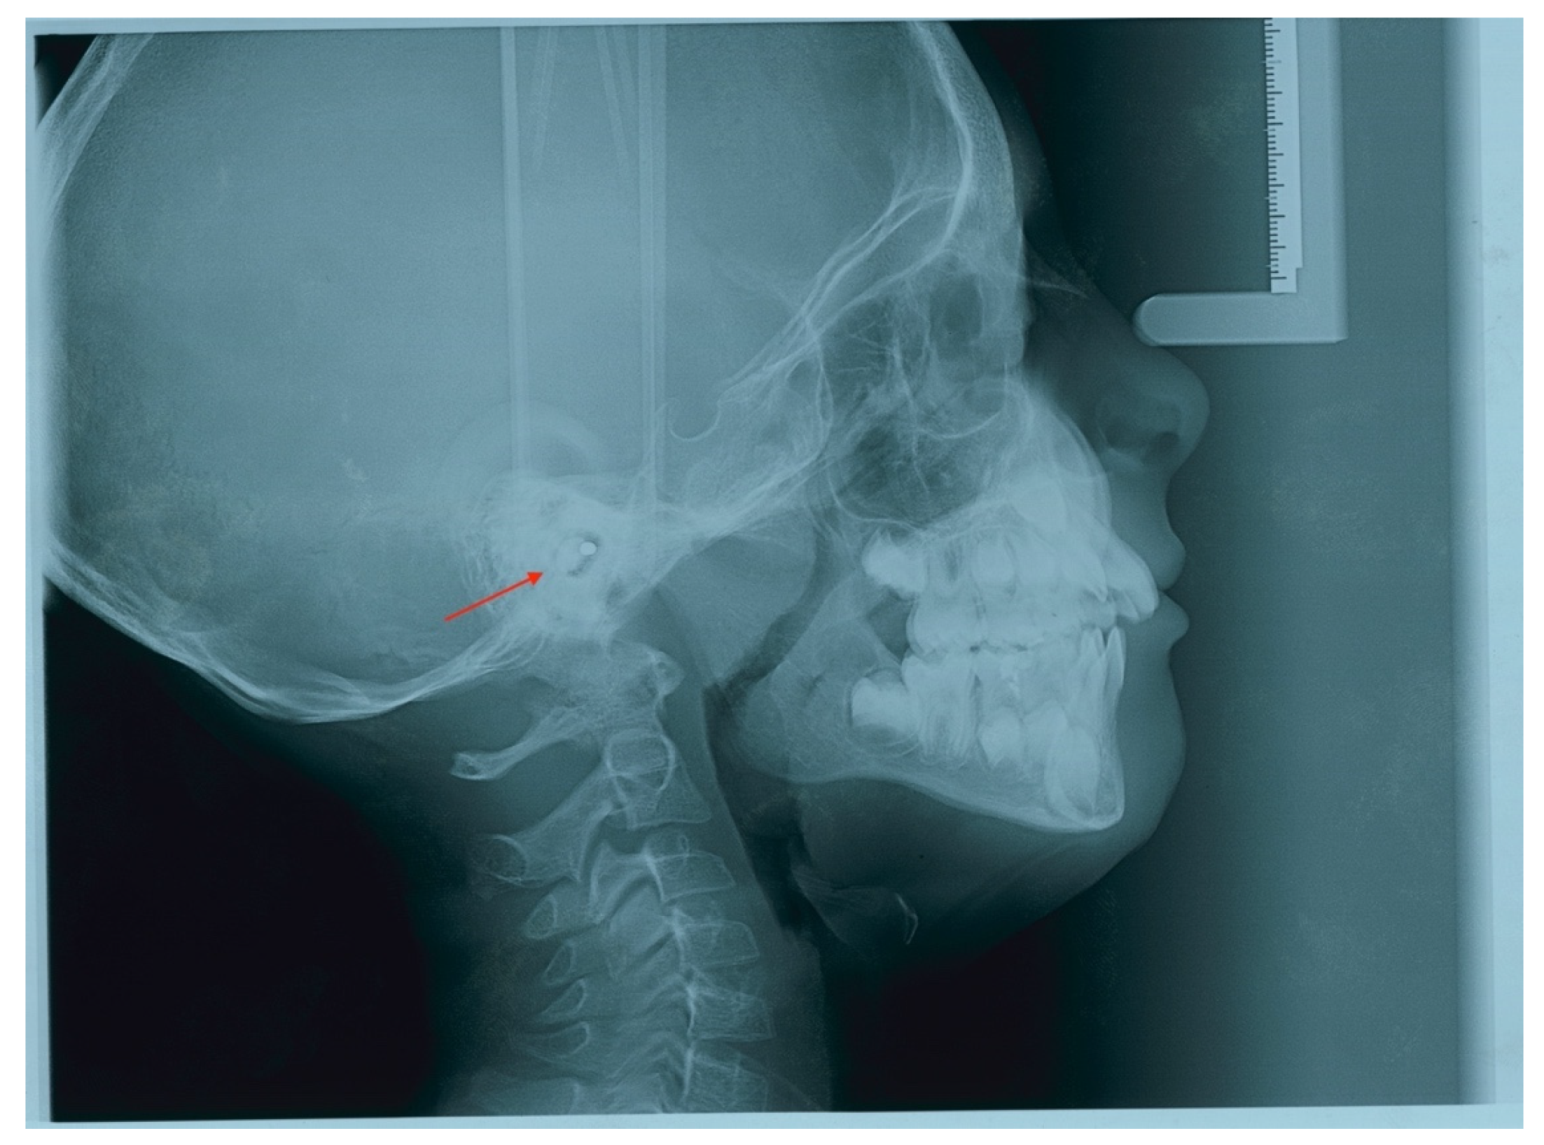

2. Case Report